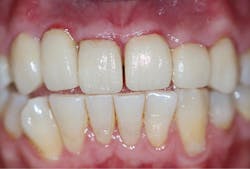

Upon his return three weeks later, the provisional was removed and the definitive laboratory-fabricated crowns were tried-in (figure 7). With excellent margins, this impression material speaks to the accuracy of capturing preparation detail, eliminating this potential concern and allowing the practitioner peace of mind.

Figure 7: Final crown try-in